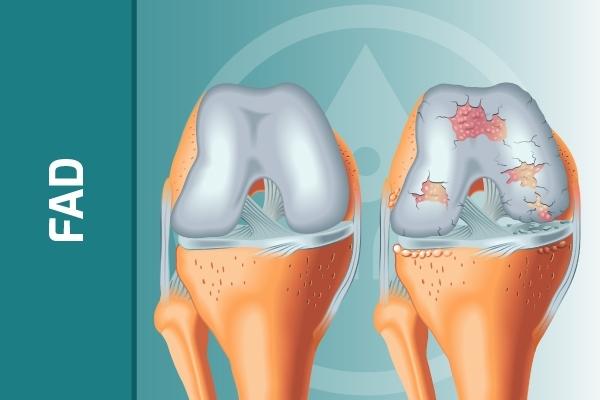

Il dolore nel ginocchio degenerativo rappresenta un aspetto di comune riscontro nella popolazione rappresentativa di questa classe di pazienti. I recenti progressi nella scienza del dolore e nella fisiopatologia della degenerazione articolare hanno migliorato la nostra capacità di gestire questa affezione molto comune, specie dopo la quinta decade di vita. Perché l'articolazione del ginocchio degenera? Quali sono i primi cambiamenti? Qual è il meccanismo del dolore? Come si valuta l'articolazione in modo da poter riconoscere precocemente il problema, quando è meglio gestirlo in modo conservativo? Cosa possiamo imparare da Cyriax su come gestire il dolore degenerativo al ginocchio? Questo corso fa il punto sulle ultime ricerche riguardo le condizioni degenerative articolari, sui loro effetti a carico dell'articolazione del ginocchio e sulla funzione generale. Vengono presentate informazioni dettagliate su degenerazione e fisiopatologia, con particolare attenzione ai migliori metodi di valutazione utili per prendere decisioni su quali pazienti devono essere indirizzati al medico e quali possono essere gestiti in modo conservativo per mezzo di principi di gestione basati sull'evidenza.

• Descrivere le caratteristiche principali del processo degenerativo dell'articolazione del ginocchio normale e patologico

• Discutere le cause specifiche del dolore nelle condizioni degenerative dell'articolazione del ginocchio